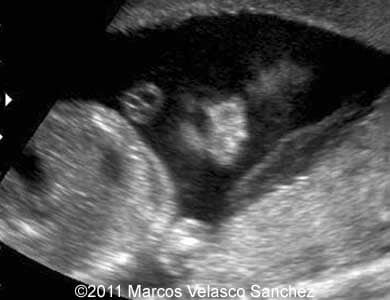

This is a case of a bilateral cleft lip associated with the cleft palate. A 25-year-old G2 P1 was referred to our department at 21 weeks of gestations. She had non-contributive personal or family history. We discovered bilateral cleft lip and palate. There were no other associated malformations.

Images 1- 4: Image 1; 21 weeks, Images 2-4; 24 weeks. Bilateral cleft lip and palate.